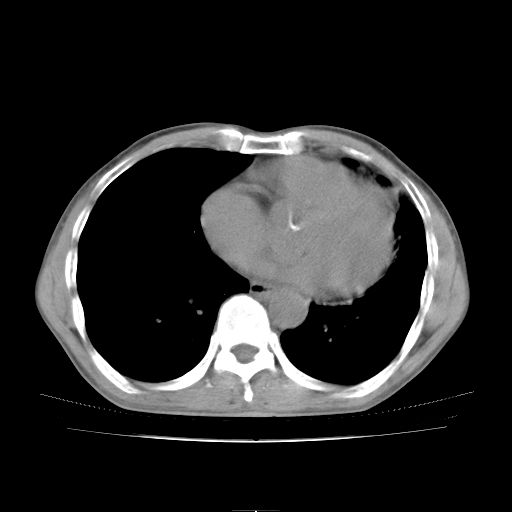

标题: CT25795:感冒后反复咳嗽两月余,痰中带血半月余。X诊断“肺 [打印本页]

标题: CT25795:感冒后反复咳嗽两月余,痰中带血半月余。X诊断“肺

1.双肺肺梗塞(理由:病灶呈三角形,与胸膜相连且局部胸膜肥厚,左心室增大)伴肺感染。

支持双肺感染,建议治疗后复查。

支持考虑双肺感染,建议治疗后复查。